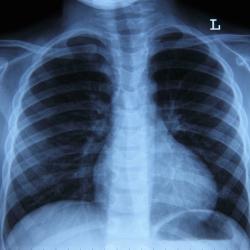

Studies have shown that for up to 5% of people, cancer moves to the cerebrospinal fluid that surrounds the brain and spinal cord or to the brain and spinal cord lining (called the leptomeninges). The condition, known as leptomeningeal disease or leptomeningeal carcinomatosis, most commonly affects those with melanoma, lung cancer or breast cancer.

Symptoms are similar to brain metastases but may also include facial or other muscle weakness or pain, difficulty swallowing, double vision and difficulty thinking clearly. The number of people developing leptomeningeal disease is increasing for the same reason that diagnoses of brain metastases are on the rise: People are living longer, giving cancer more time to spread. Doctors use MRIs and spinal taps (lumbar punctures), to make a diagnosis.